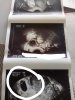

Ja mialam tez taka sytuacje ale okazało się że to nie cialko zolte a jedynie jakas czesc pecherzyka. Zaraz poszukam zdjęcia i wstawię. Lekarze myśleli że to pecherzyk zoltkowy a jednak nie. Za każdym razem od lekarzy slyszalam ze jesli jest pecherzyk bedzie tez zarodek.

• USER_SCOPED_TEMP_DATA_orca-image-1603103238325_6723902324923471091.jpeg

USER_SCOPED_TEMP_DATA_orca-image-1603103238325_6723902324923471091.jpeg

167,4 KB · Wyświetleń: 72